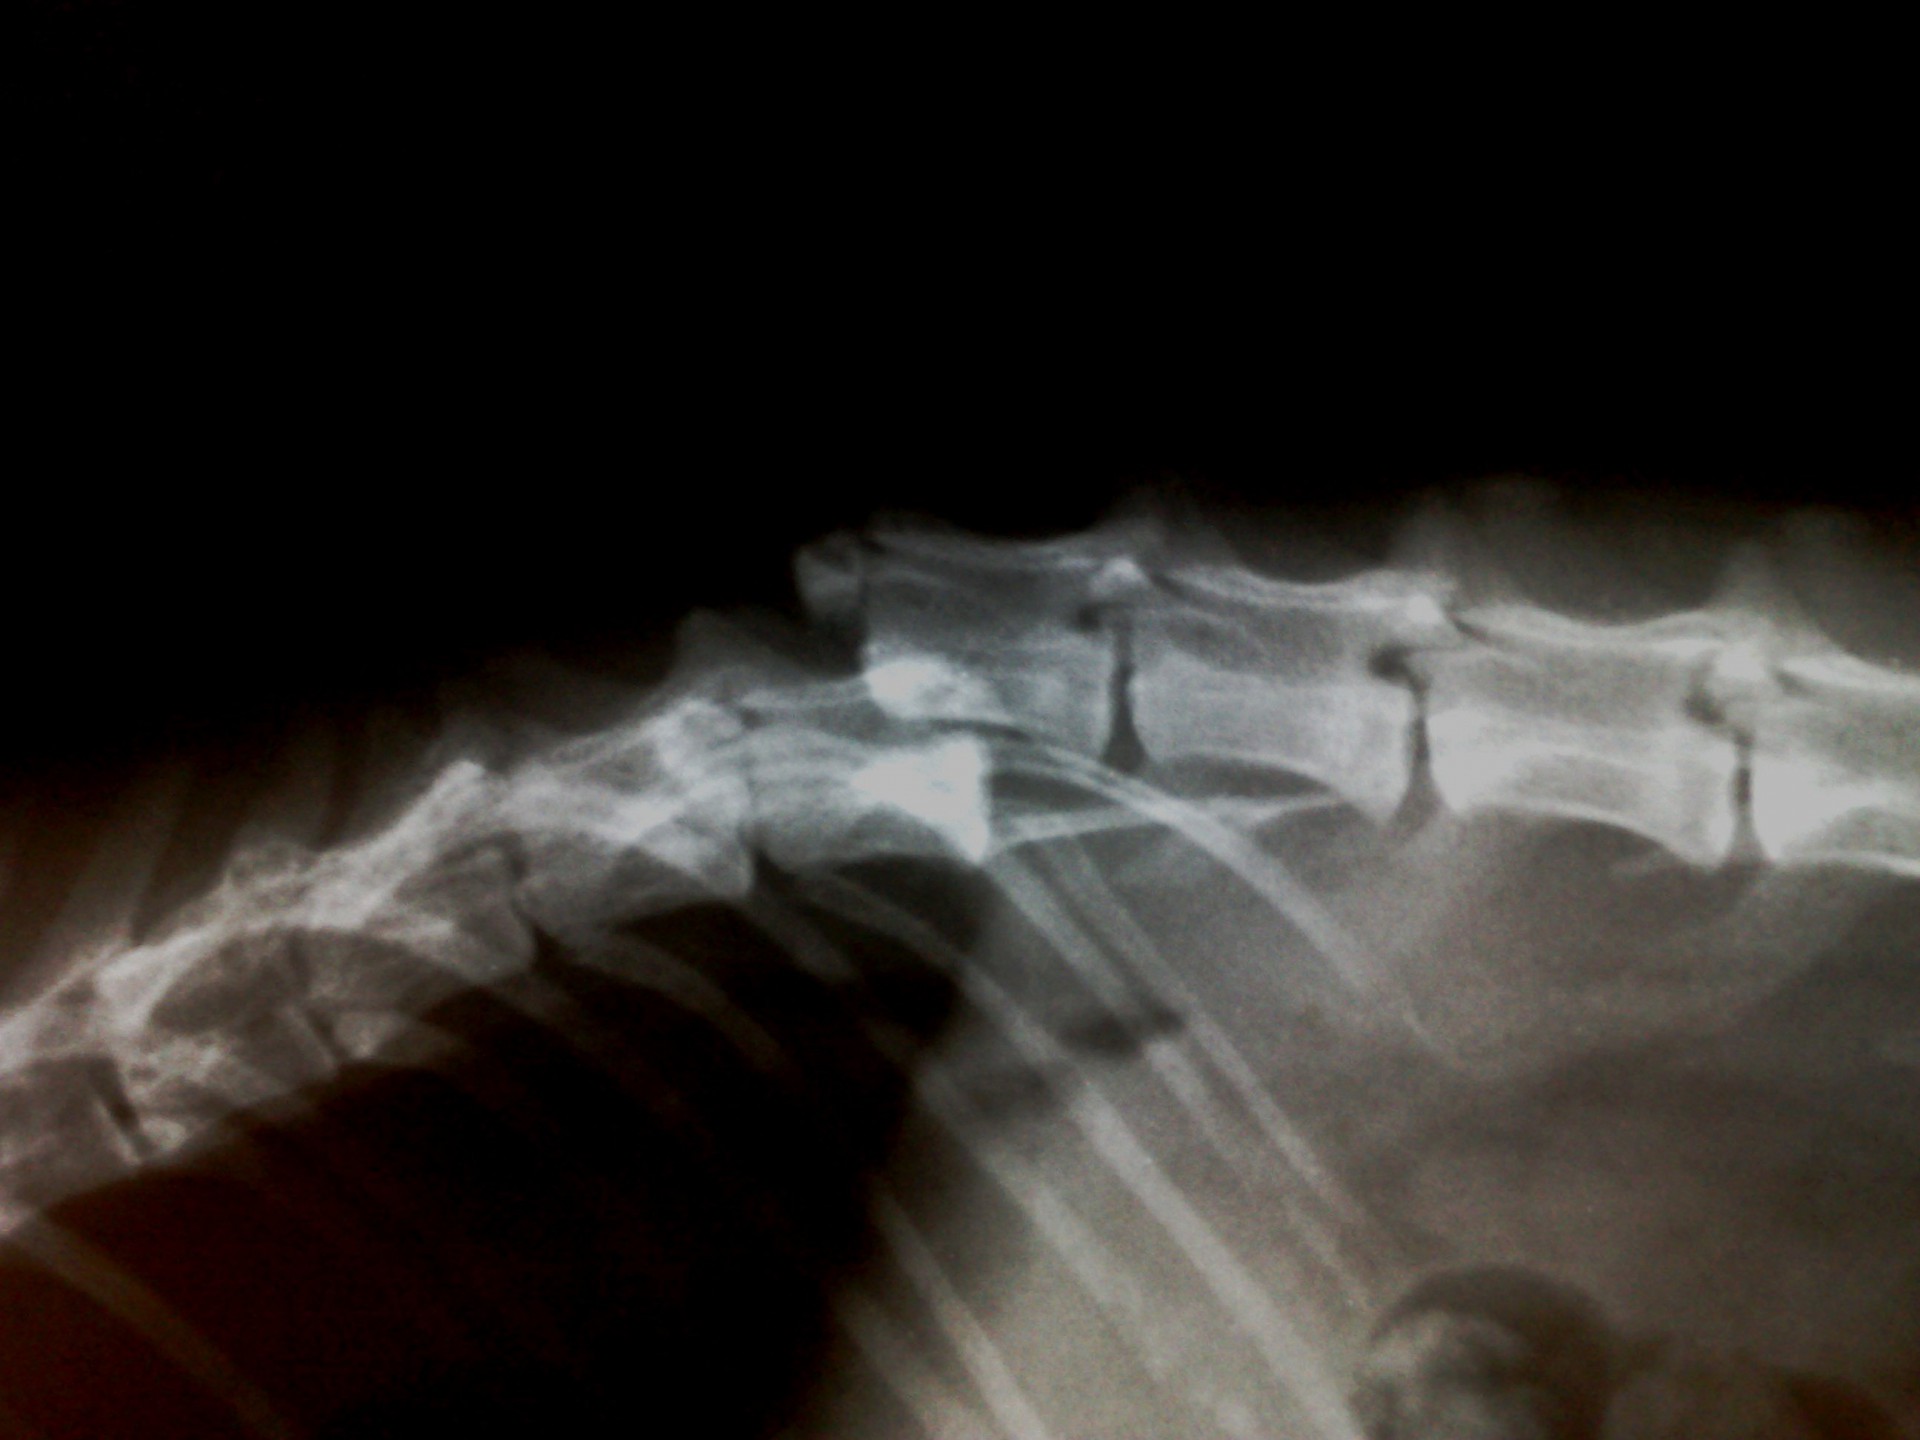

A gerinctörések műtéti ellátása kettős feladatot jelent: egyrészről a törés és elmozdulás következtében kialakult gerincvelő összenyomatást kell megszüntetni, másrészről a tört végeket kell adaptálni és eredeti állapotban - a további elmozdulás megakadályozása érdekében - rögzíteni. A műtéti ellátás során ezért minden esetben az érintett területen a gerinccsatorna felső csontos ívét eltávolítjuk (total laminectomia) így a gerincvelő sérülésének mértéke egyértelműen látható ill. a későbbi összenyomatása elkerülhető.

A törött csigolyatestek adaptációja és rögzítése a nyitott gerinccsatorna mellett komoly kihívást jelent. A későbbi elmozdulás elkerülésére többféle műtéttechnika alkalmazható, melyek közül a csigolyatestek lemezes osteosynthesise ill a fixateur interna használata terjedt el leginkább. Első esetben a sérülés előtti és mögötti csigolyákat lemez és csavarok segítségével egymáshoz rögzítjük, míg az utóbbi esetben a törés előtti és mögötti egy vagy több csigolyatestet két oldalról behelyezett csavarok és egy steril kétkomponensű akrilát műgyanta segítségével rögzítjük.